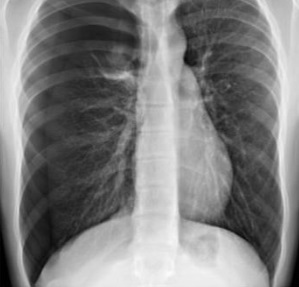

¿Cuál es el dx?

Neumonía